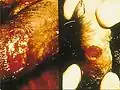

Projev nemoci na penisu | |

Inkubační doba nemoci se pohybuje od 1 do 12 týdnů.[2] Po uplynutí inkubační doby se začne tvořit vřed, častěji větší množství vředů. Ty se posléze spojují, praskají, krvácejí a značně destruují nejenom tkáň pohlavního ústrojí, ale i tkáň řitního otvoru a třísel.[2] Ve stejnou dobu probíhá hojení prostřednictvím vazivových jizev. Neléčená nemoc může způsobit vážné následky. Terapie probíhá podáváním antibiotik či sulfonamidů,[3] někdy je však nezbytný chirurgický zákrok.[2]